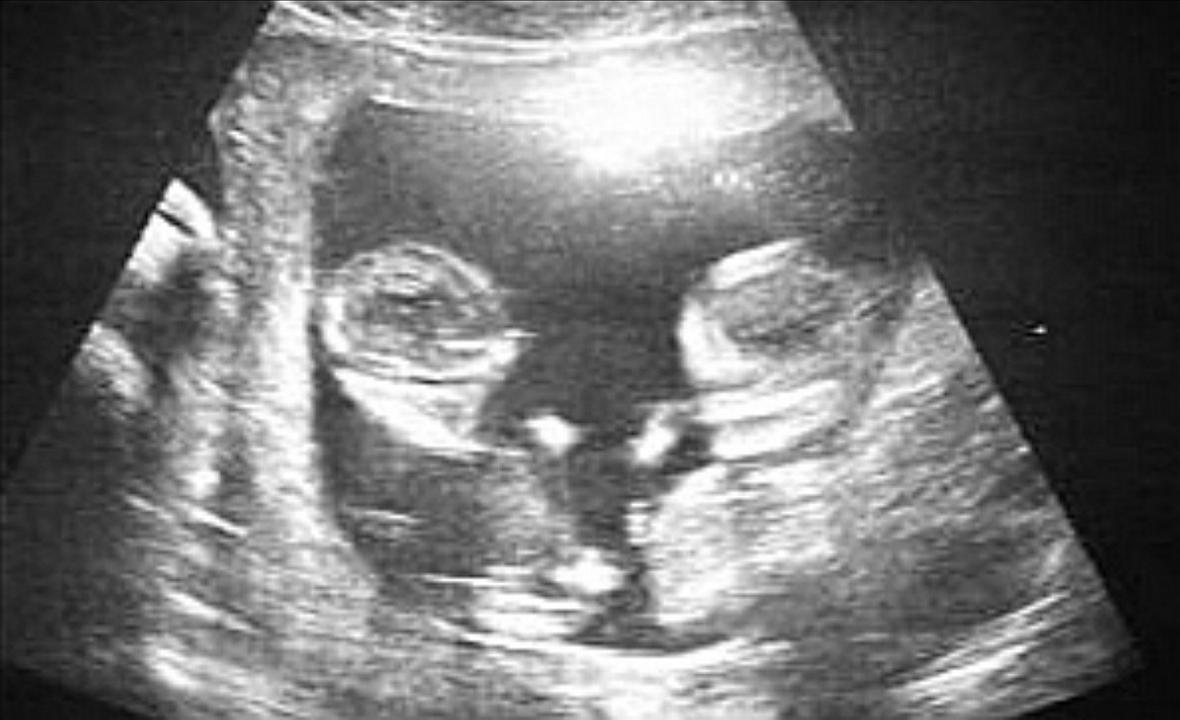

我的双胞胎崽儿nt已顺利完成00